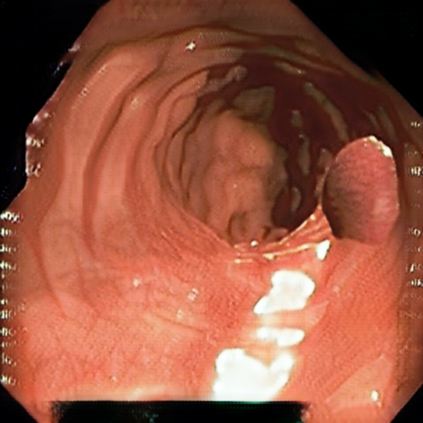

Deep learning has shown excellent performance in analysing medical images. However, datasets are difficult to obtain due privacy issues, standardization problems, and lack of annotations. We address these problems by producing realistic synthetic images using a combination of 3D technologies and generative adversarial networks. We use zero annotations from medical professionals in our pipeline. Our fully unsupervised method achieves promising results on five real polyp segmentation datasets. As a part of this study we release Synth-Colon, an entirely synthetic dataset that includes 20000 realistic colon images and additional details about depth and 3D geometry: https://enric1994.github.io/synth-colon